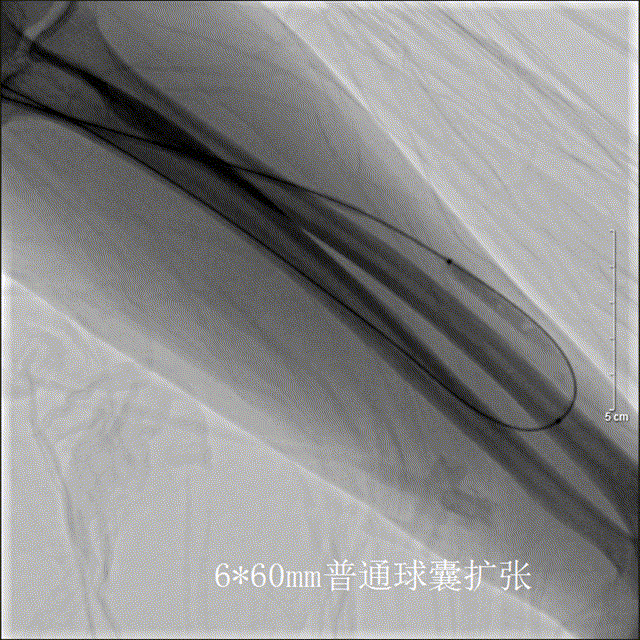

6*60mm普通球囊数次扩张,狭窄段不能充分扩开

改用6*40mm高压球囊数次扩张狭窄段仍不能充分扩开